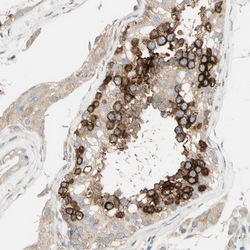

Supportive validation

- Submitted by

- OriGene (provider)

- Main image

- Experimental details

- Immunohistochemical staining of human testis shows strong cytoplasmic positivity in cells in seminiferus ducts.Antibody dilution:1:500. Image and statement courtesy of the Human Protein Atlas (HPA).

- Validation comment

- IHC